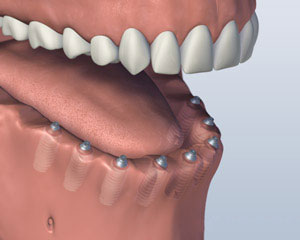

个人种植体

最后一个选项是让所有你的牙齿单独更换,使他们看起来是生长出来的牙龈组织,将最相似的天然牙的外观. 此选项通常需要八个或更多 植入物. 单独的基牙或这些植入物中的每一个支撑柱将被制成,每个缺齿冠将被放置. 牙齿往往是结合在一起的 窦嫁接 更换骨高度实力作支撑. 总体, 这是最昂贵的选择, 因为它需要最植入物和个体替代牙制作. 您所更换的选项也可以通过您的颌骨的电流大小和形状的限制.

1. 之前

2. 植入放置

3. 修复完成